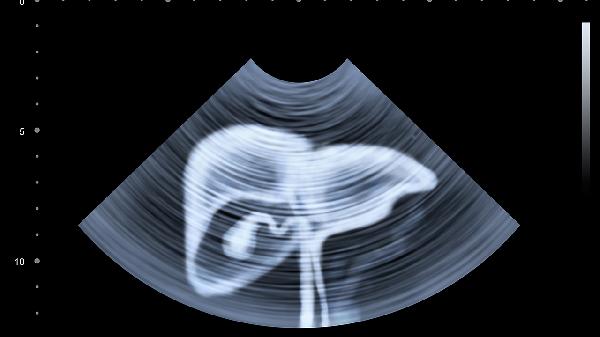

肝脏超声检查是利用超声波对肝脏进行成像的无创检查方法。通过超声检查可以观察肝脏的大小、形态、边缘、内部回声等特征,发现肝脏占位性病变、脂肪肝、肝硬化等异常改变。超声检查具有操作简便、无辐射、可重复进行等优点,是肝脏疾病筛查和随访的重要检查手段。对于可疑肝脏病变,超声检查常作为首选影像学检查方法。